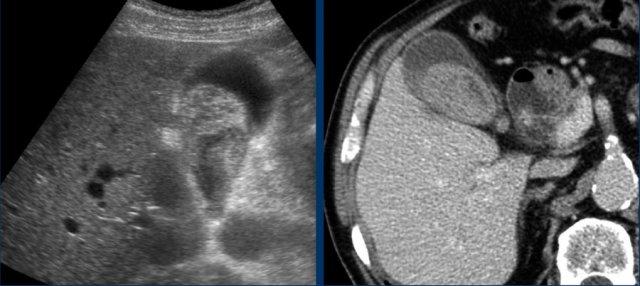

Đây là hình ảnh của một bệnh nhân cao tuổi (79 tuổi) với đau hạ sườn phải cấp tính.

Túi mật lớn, tuy nhiên không phình nước (đầu mũi tên) với sỏi di động và dày thành phù nề.

Xét nghiệm cho thấy CRP 3 và amylase huyết thanh 985.

Chẩn đoán: viêm tụy cấp do sỏi mật với dày thành túi mật thứ phát.